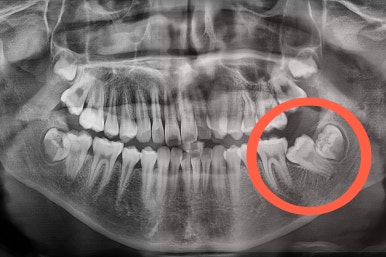

X-ray를 보면 사랑니가 어부바 하고 있어서 나와야 될 어금니가 짓눌려 있는 양상이었어요.

이 경우 방향을 잘못잡아서 바로 앞 어금니도 밀어버리거나 해를 가할 수 있는 상황이었어요.

사랑니가 잘못나는 바람에 사랑니 포함 치아 3개가 문제가 될 수 있는 상황이었어요.